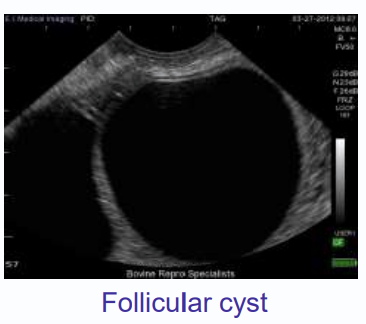

follicular cysts

thin walled, less than 3 mm thick

several large cyst or multiple small cysts

produces estrogen

clinical presentation for follicular cysts

anaestrus, nyphomania (estrus like behavior), virilism (male characteristics)